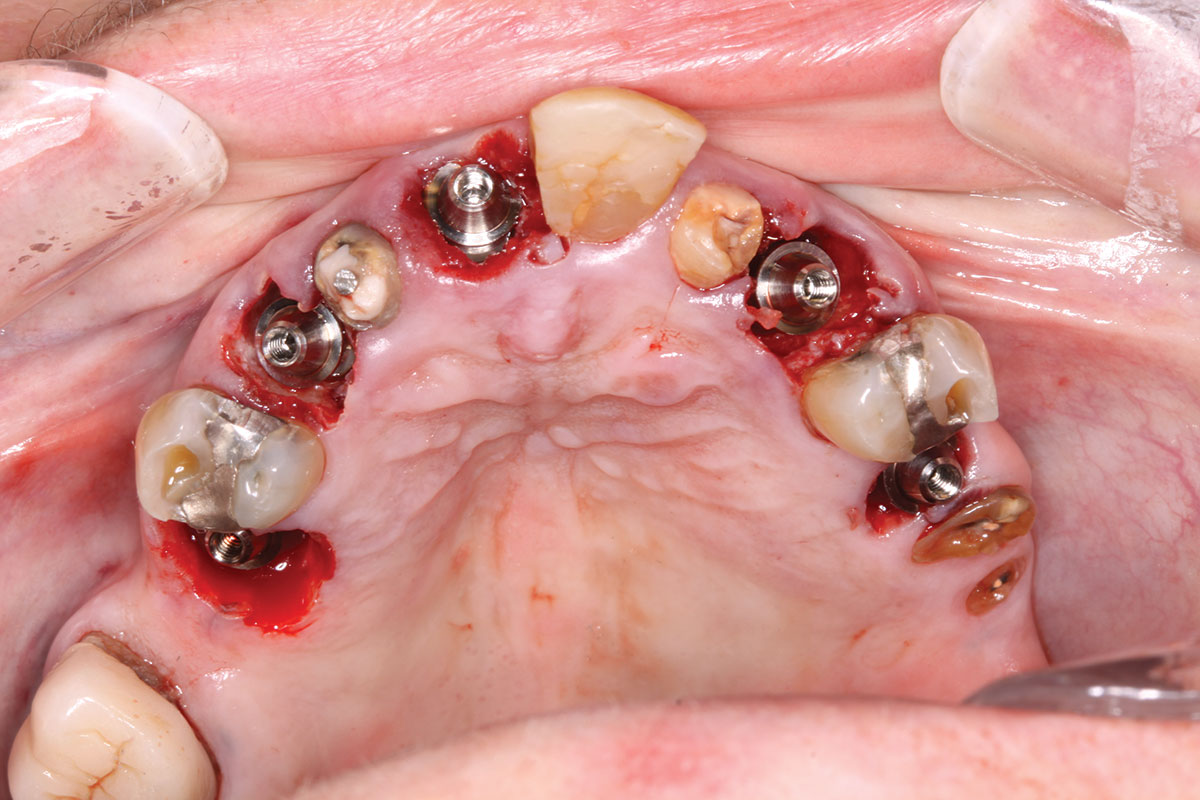

A maxillary intraoral scan was obtained with a digital scanner capturing the two remaining teeth in sites Nos. 5 and 12 and the scan gauges on implants Nos. 8 and 11. Subsequently, teeth Nos. 5 and 12 were extracted. Scan gauges were placed on implants Nos. 4, 6, and 13. At this time, another intraoral scan was captured of all the scan gauges on the five implants with the surrounding soft tissues (Figure 14 and Figure 15).

Fig 14. All implants, multi-unit abutments, and scan gauges in place.

Figure 14

Fig 15. Completion of maxillary flapless immediate implant surgery and placement of multi-unit abutments.

Figure 15